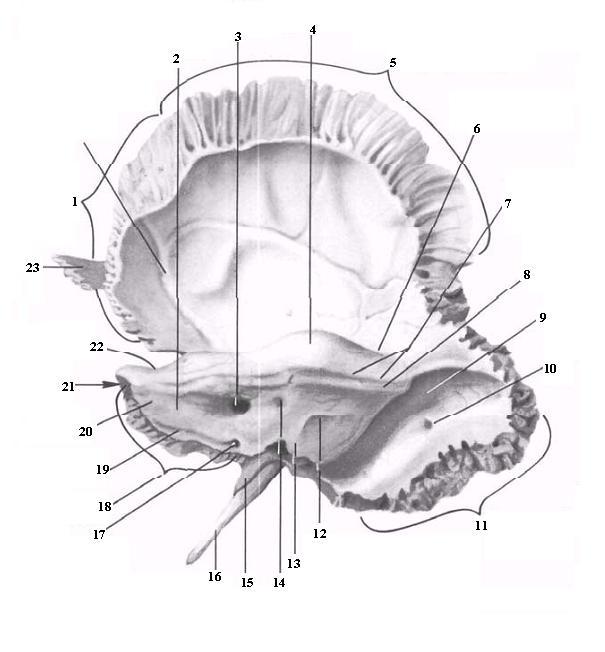

Анатомия и особенности фиссуры петротимпаника